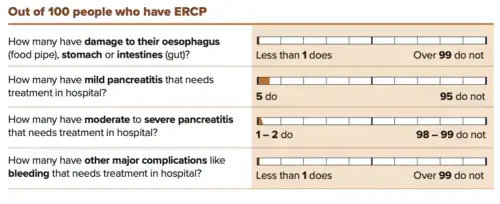

Obstruction of the common bile duct with gallstones can sometimes be relieved by endoscopic retrograde sphincterotomy (ERS) following endoscopic retrograde cholangiopancreatography (ERCP).[58]